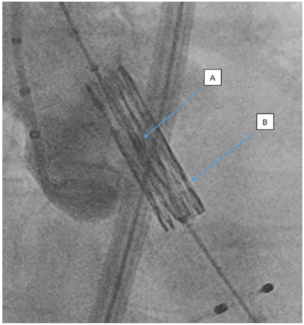

Garcia TVT Bioprosthetic valve fracture

Valve-in-Valve

Sapien 3 Valve

TAVR Valve Deployment